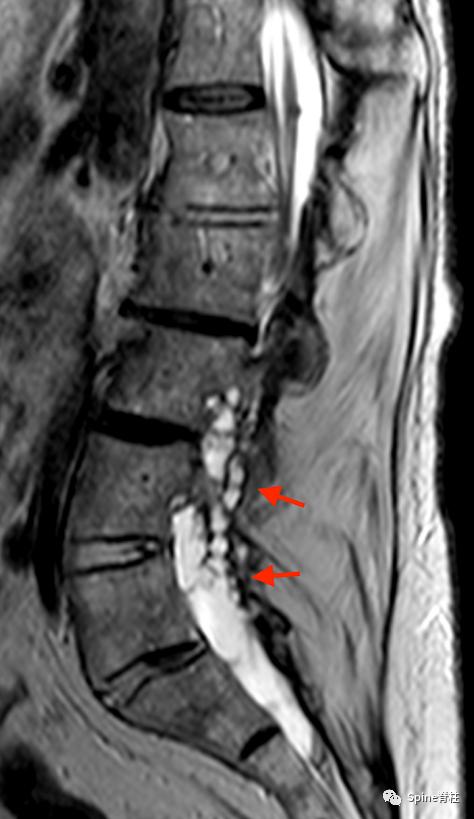

矢状位T2(a)和T1(b)加权像提示下胸椎和上腰椎硬膜扩张伴显著的椎体后壁扇形凹陷(红色箭头)。轴位T2(c)和T1(d)加权像提示硬膜囊外侧膨出(绿色箭头)伴椎体扇形缺损。蓝色箭头是指继发于皮肤神经纤维瘤的多发性皮肤结节